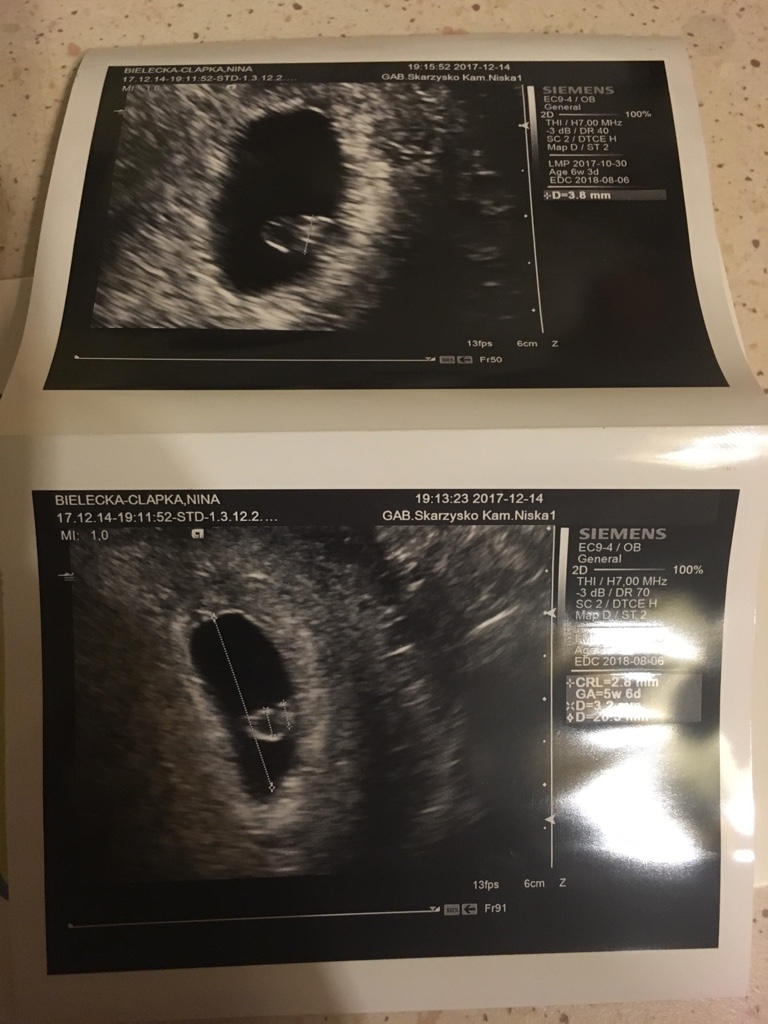

- na USG wg OM 6tc+6dni- nie było widać zarodka, tylko pęcherzyk żółtkowy w jaju płodowym. Dwóch lekarzy sugerowało puste jajo/obumarły płód. Beta wynosiła ponad 10 tysiecy i zaczęła rosnąć powoli (ok. 30% co 48h). Przeplakalam 2 dni i zgodnie z zaleceniem lekarza pojechałam do szpitala (ktore mogło sie skonczyć łyżeczkowaniem).

W szpitalu mnie zbadali i zarodek się pojawił 0.37 cm, jeszcze bez serduszka... Wg OM to 7tc + 3 dni, wg USG 6tyg+0 dni. Wielka radość i strach przed kolejnym rozczarowaniem. W piątek 22.12. będę mieć kolejne usg i dowiem się, czy dzidzia rośnie i czy bije jej serduszko. Trzymajcie kciuki.